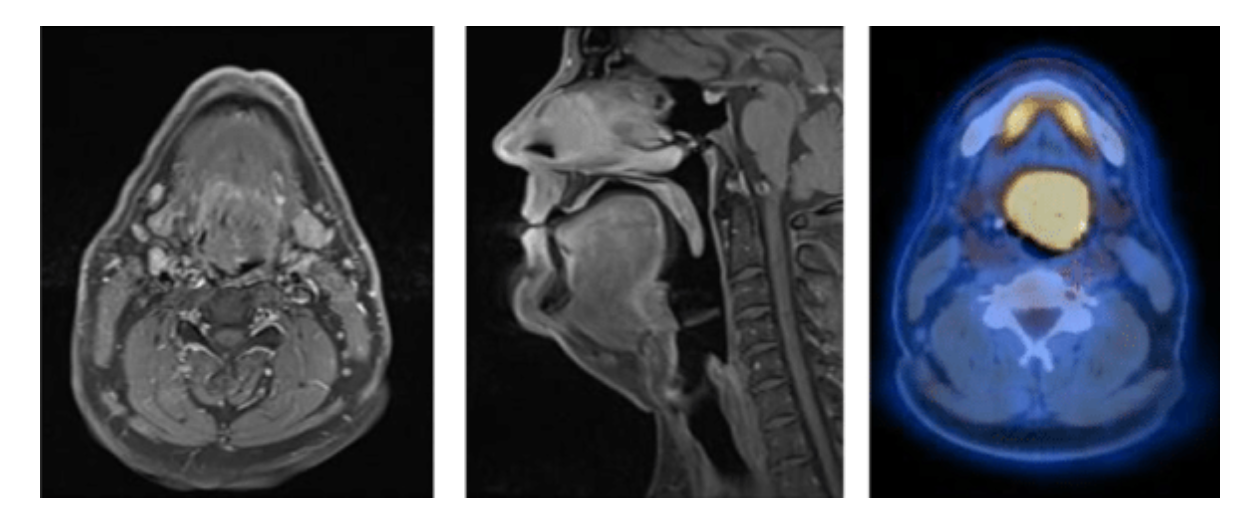

Homem, 49 anos, encaminhado para investigação devido lesão de crescimento rápido em base de língua há 4 meses. Ressonância magnética de cabeça e pescoço confirmou lesão infiltrativa, sem plano de clivagem com as estruturas adjacentes. PET/CT evidenciou hipermetabolismo glicolítico (SUVmáx 16) restrito à cavidade oral. Biópsia incisional foi compatível com SARCOMA HISTIOCÍTICO. Neste caso, qual marcador imunohistoquímico deve estar AUSENTE?

C) CD1a

O CD1a é uma molécula relacionada ao complexo maior de histocompatibilidade, forma um heterodímero com a beta-2 microglobulina e participa da apresentação de antígenos lipídicos e glicolipídicos para as células T.

A presença de CD1a é típica da histiocitose de células de LANGERHANS, que também expressa a proteína LANGERINA.

Outra doença que também apresenta expressa CD1a é a leucemia linfoblástica de células T com imunofenótipo CORTICAL, que coexpressa CD4 e CD8.

O perfil histoquímico típico do sarcoma histiocítico é CD45 positivo, CD163 positivo, CD68 positivo, lisozima positiva e CD4 positivo.

NÃO há presença de marcadores relacionados à histiocitose de células de Langerhans, como CD1a e langerina.